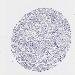

OVARIAN CANCER - Protein expressioni

A mouse-over function shows sample information and annotation data. Click on an image to view it in a full screen mode. Samples can be filtered based on level of antibody staining by selecting one or several of the following categories: high, medium, low and not detected. The assay and annotation is described here.

Note that samples used for immunohistochemistry by the Human Protein Atlas do not correspond to samples in the TCGA dataset.

Antibody stainingi

Antibody staining in the annotated cell types in the current human tissue is reported as not detected, low, medium, or high, based on conventional immunohistochemistry profiling in selected tissues. This score is based on the combination of the staining intensity and fraction of stained cells.

Each image is clickable and will lead to virtual microscopy that enables deeper exploration of all samples and also displays staining intensity scores, fraction scores and subcellular localization as well as patient and tissue information for each sample.

Antibody HPA036348

Antibody HPA036349

Antibody CAB002422

Antibody CAB005258

Cystadenocarcinoma, serous, NOS

Carcinoma, NOS

Cystadenocarcinoma, mucinous, NOS

Carcinoma, endometroid